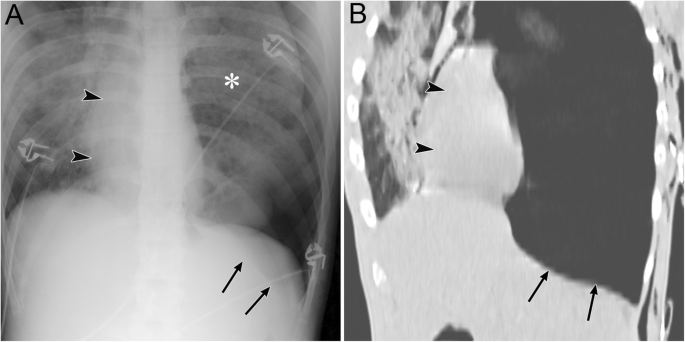

Tension pneumothorax due to traffic trauma in an 18-year-old man. a A supine radiograph shows left pneumothorax with a rightward mediastinal shift (black arrowheads) and partly inverted left hemidiaphragm (black arrows). The left lung is collapsed with a contusion (asterisk). b A coronal CT image clearly depicts a rightward mediastinal shift (black arrowheads) and an inverted left hemidiaphragm (black arrows)

Tension pneumothorax (I-5)

Tension pneumothorax is characterized by an abnormal increase in the pressure of the involved thoracic cavity. A one-way valve between the involved lung and the pleura leads to the continuous leakage of air into the pleural cavity and causes the accumulation of air within the pleural cavity [30]. Next, the ipsilateral lung collapses, the mediastinum is displaced away from the affected side, and the ipsilateral diaphragm is displaced downwards (especially in positive pressure ventilation) and may invert downwards [30]. The cardiac output is reduced because of the impaired venous return [30], and cardiac arrest eventually ensues [30]. Tension pneumothorax is a life-threatening event that occurs in the ICU; thus, it should be identified immediately, especially in patients who are treated with positive pressure ventilation. Immediate decompression of the thorax is mandatory in such cases [12].

Radiographic findings of the lung in tension pneumothorax are the same as those of the lung in a simple pneumothorax. In addition, mediastinal displacement, diaphragmatic inversion, increased intercostal space, and total or subtotal lung collapse reflect the expansion of the affected hemithorax (Fig. 7) [19, 31]. A more important sign of tension pneumothorax is the flattening of the heart border, SVC, and IVC [19]. This sign reflects impaired venous return [19].